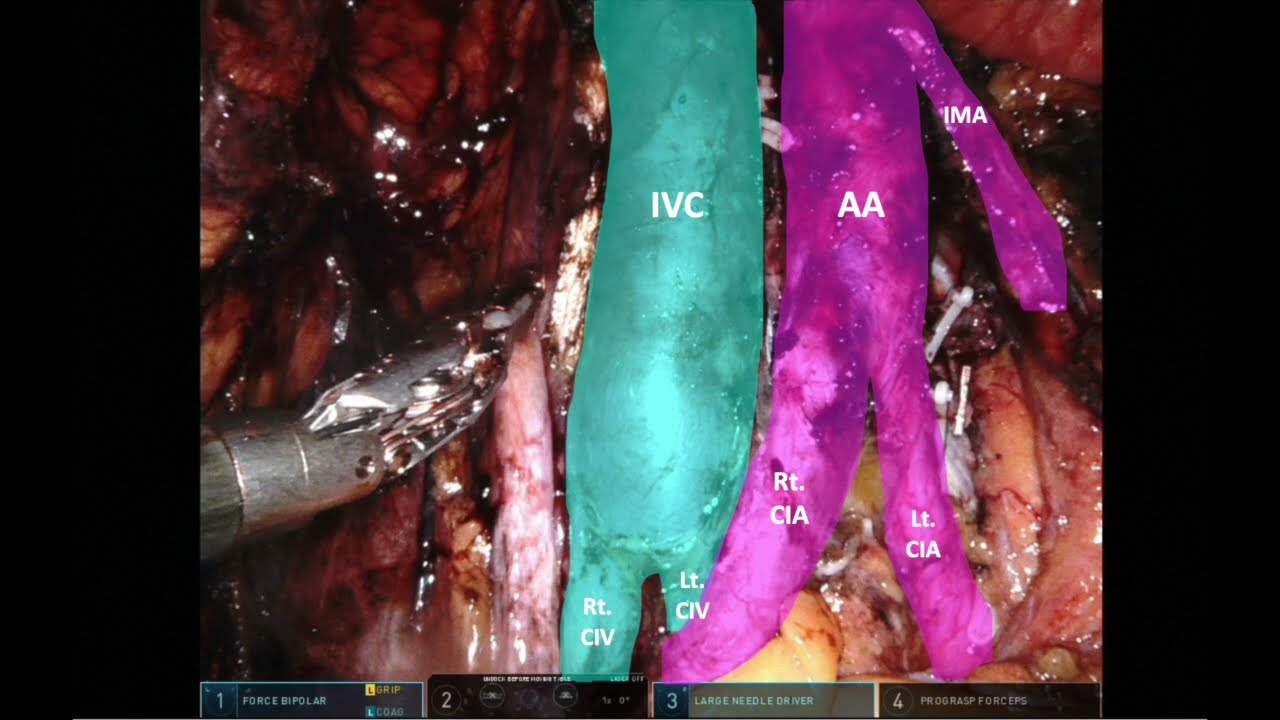

#306 Single port urinary diversion in a hostile abdomen- Dr. Neerja Tillu

KS Awards, Robotics, Surgeon ';